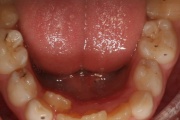

Ruumipuudus eesmiste hammaste osas

Ruumipuuduses ja viltuselt seisvad esihambad on sagedaseim põhjus, miks lapsevanem ise oma lapse ortodontid juurde toob. Lõualuude hea asetuse korral ei ole varane ravi vaheldusvas hammaskonnas ruumipuuduse korrigeerimiseks enamasti näidustatud, sest see probleem on sama hästi korrigeeritav Loe edasi »